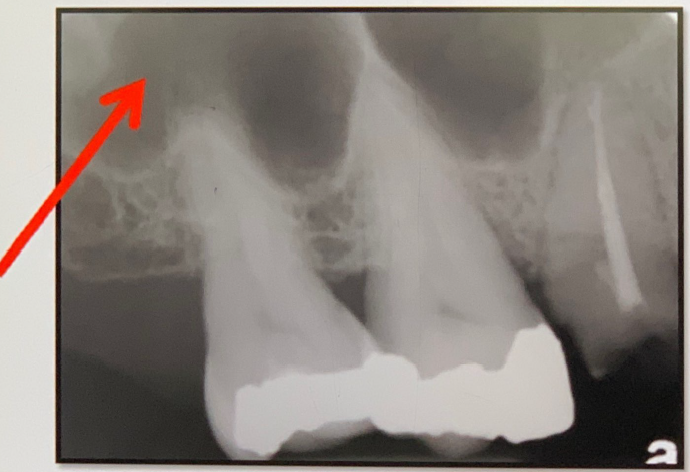

95. What is showing by red arrow?

External Oblique Ridge a continuation of the anterior border of the mandibular ramus. It follows an anteroinferior course lateral to the alveolar process.